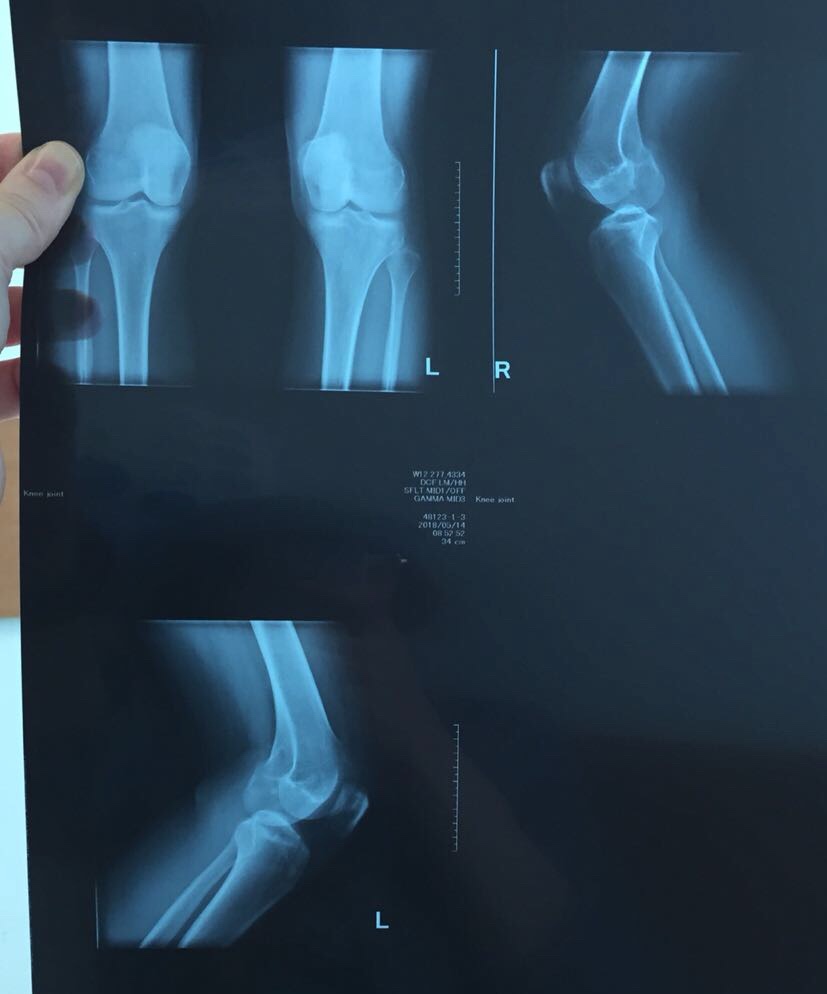

Рекурвация коленного сустава: рентгеновские снимки и объяснения